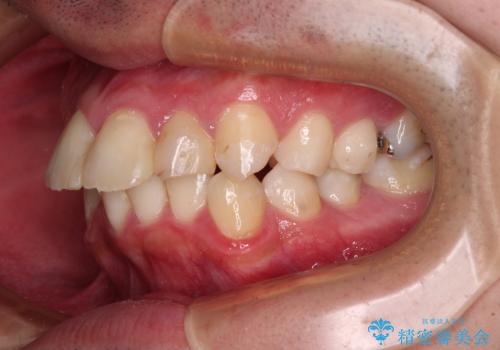

- 口元の突出感と奥歯の咬み合わせの悪さを気にして来院された患者様です。

口元はやや突出感があったため、上下左右の第一小臼歯4本を抜歯してワイヤー矯正にて抜歯矯正を行うこととしました。

また、左右ともに最後臼歯が交叉咬合になっており、外側に飛び出している上顎の最後臼歯を補助装置を利用して、積極的に内側に引き込むようにしました。

2年半の治療期間を想定しており、予定通りの期間で無事に終了することができました。

唇や顎先に力を入れないなくてもスムーズに唇を閉じることができるようになりました。